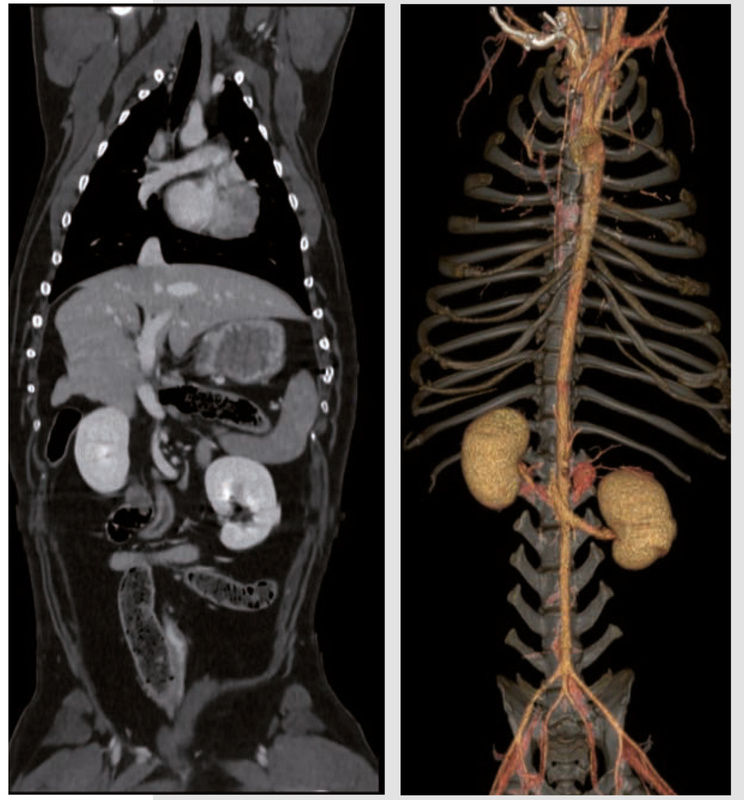

- Risoluzione spaziale di 18 lp/cm per consentire l’imaging di alta qualità e la visualizzazione dell’anatomia in 3D